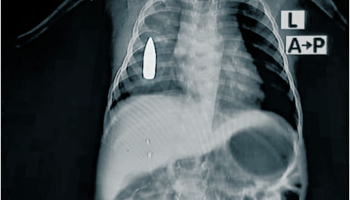

El 16% de los heridos de guerra atendidos en un hospital del sur de Jartum son niños

Algunos procedimientos de cirugía no son posibles por el bloqueo de material quirúrgico y la peligrosidad de las rutas impide derivar pacientes a otros centros